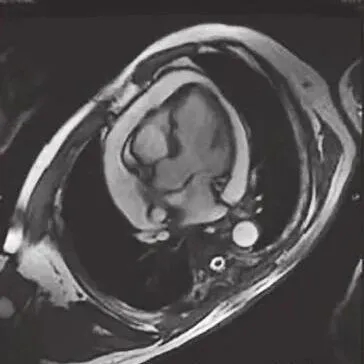

静息状态下可见左室前间壁心尖段、室间隔及左室前壁心尖段室壁变薄(约4mm),回声偏低,运动明显减弱;心包检查可见中-大量液性暗区包绕心脏,心脏呈“摆动征”;右房、右室受压变小(图3)。

图3入院时超声心动图

左室前壁右室梗死的超声心动图特征为于心尖四腔心切面显示室间隔心尖段运动异常,并延续至右室心尖部,可累及右室游离壁近心尖区。右室心尖部运动异常区呈正三角形,宽底在右室心尖1/3处,梗死顶部指向心底部。右室游离壁破裂的超声心动图表现为:①右室游离壁破口对应的心包腔内可见不同程度的液性暗区;心包腔内液性暗区迅速增宽为心脏压塞的特征性图像改变,彩色多普勒于相应切面可见心包腔内液性暗区中红或蓝色血流束,由穿孔处至心包腔;②穿孔的室壁可于相应心腔切面上呈现心室壁回声中断;穿孔部位的心肌较薄且运动失常;③由于心包腔内压力增高,心室收缩力减弱,穿孔处的血流速度多较低。心肌破裂处无论位于前壁或下壁,均为纵行裂口,表层裂口较大,里层较小,常常形成迂曲不整的孔道。由于右室解剖形态的特殊性,并受常规心脏超声切面观察角度的局限,本例患者多次超声检查均未能明确破口位置,是诊断困难的原因之一。心包积液临床症状的发生主要是由于大量心包积液压迫心脏和周围器官及组织所引起,取决于心包腔内的液体量、液体蓄积增加的速度和心包的特征。当心包腔内液体量缓慢增加时,有一定弹性的心包被扩展以接受所增加的液体量,而心包腔内压力几乎不变。在此情况下,心包腔内液体蓄积可达2000ml而不引起心包腔内压力升高。相反,若心包腔内液体量增加迅速,即使200ml也可引起心包腔内压力急剧升高,使心脏受压而产生血流动力学变化。本例患者第一次心包穿刺引流量为560ml,此后间隔2~3个月定期复查并先后行4次心包穿刺,引流量分别为1370ml、590ml、920ml、970ml,性质相同,均为血性心包积液。曾反复行肿瘤、结核及其他病原学相关检查,未见阳性发现。考虑存在超声无法探明的心肌梗死后心肌微小破裂,保守治疗未能正常愈合,致血液持续渗出心包腔,为了证实这一推论,又对患者进行了心肌声学造影及增强磁共振成像,结果示心肌声学造影无异常发现,增强磁共振成像可见存在心包腔至心室方向的湍流信号,提示心肌微小裂孔的可能。因右室压力显著低于左室,渗液速度缓慢,故未引起急性心脏压塞症状,是临床诊断的干扰因素,也是患者得以幸存的原因。